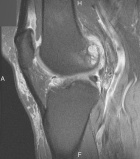

P.P. - 55 year old female c/o right knee pain x 1.5 years. Pain is dull, intermittent, worse with activity. No mechanical symptoms. No history of trauma. Treatment with NSAIDs, aspirations, viscosupplementation, intraarticular steroids provide minimal relief.

Zoom image: Radiological image Radiological image.